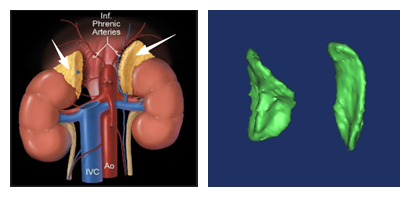

(注:图中白色箭头所示,正常肾上腺三维形态呈三叶草形,边缘光滑,密度均匀,位于肾脏上方,但与肾脏相互独立。)